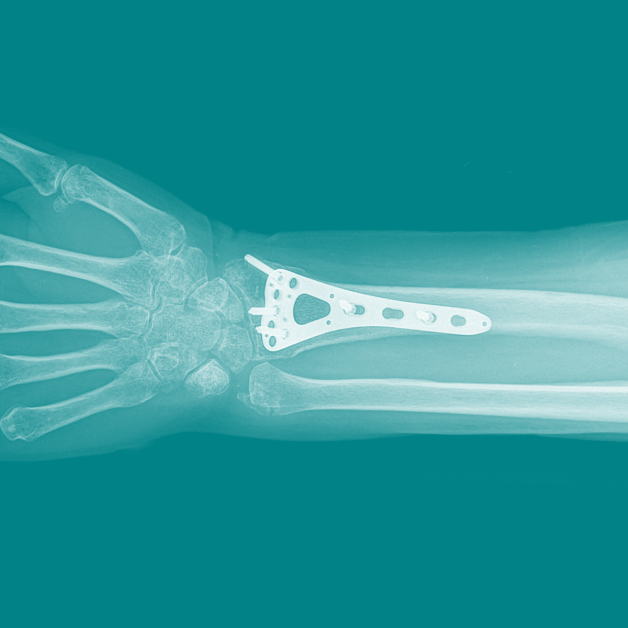

Dezvoltarea tehnicilor chirurgicale și metodelor inovative de tratament le permite chirurgilor să fixeze oasele fracturate din interior, cu risc minim și rezultat net superior. Fixarea chirurgicală presupune alinierea corectă a osului și prinderea acestuia cu tije, implanturi, astfel încât poziția să rămână stabilă, exact cum era înainte de fracturare.

Scopul tratamentului chirurgical al fracturilor este repoziționarea fragmentelor osoase, alinierea la poziția naturală și fixarea cu ajutorul unor implanturi speciale, plăci, șuruburi, tije și broșe.

Implanturile utilizate la Medpark sunt de cea mai înaltă calitate, realizate din oțel inoxidabil și titan, fiind durabile și totodată total compatibile cu organismul, astfel încât să nu provoace reacții adverse. Departamentul de traumatologie dispune de cea mai vastă gamă de materiale de diferite mărimi și forme pentru a se adapta perfect osului fracturat al pacientului, ceea ce este extrem de important pentru libertatea mișcării.

Planificarea intervenției se realizează doar în urma diagnosticului imagistic prin radiografie sau tomografie computerizată, care confirmă necesitatea și tipul de tratament. Intervențiile chirurgicale sunt indicate în cazul fracturilor complexe cu deplasare și luxație, când aplicarea de ghips este ineficientă și dăunează articulațiilor. Medicul va decide tactica cea mai potrivită de tratament pentru fiecare pacient în parte.

Intervenția se realizează sub control radiologic intraoperator, ceea ce permite vizualizarea imediată a rezultatelor.